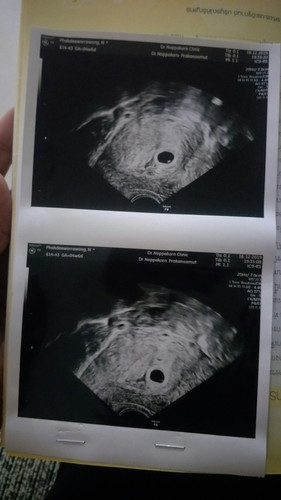

4w+6d ยังไม่เจอตัวอ่อน

มีแม่ๆคนไหน ซาวด์ตอนครรภ์อ่อนๆเท่านี้แล้วเห็นถุงตั้งครรภ์แล้วบ้างคะ จากท้องแรกแท้งไปตอน8วีค ตอนนี้ท้อง2 ได้4w6d หมอนัดอีก2อาทิตย์ ถ้ายังไม่เจอสันนิฐานได้ว่าท้องลม แม่ๆท่านไหนมีประสบการณ์แชร์ให้ฟังหน่อยค่ะ รู้สึกกังวลมาก ขอบคุณค่ะ

แฟนเราตื่นเต้นรีบพาไปฝากครรภ์คะ อายุครรภ์เท่าไรตอนนั้นไม่ทราบ ซาวไม่เจออะไรเลย กลับบ้านมาจิตตกมากคะ หมอนัดอีก2อาทิตย์ เจอถุงครรภ์ 6w2d ค่ะ ตอนแรกที่ไม่เจออะไรเลยก็น่าจะอายุครรภ์4w2d คะ